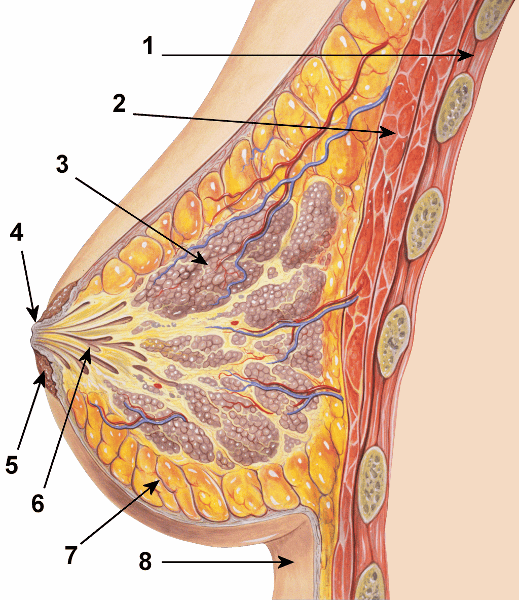

Areola

Lactiferous duct

Mammary glands